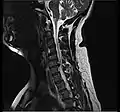

Herniated disc at C6–C7 level

Cervical disc herniations occur in the neck, most often between the fifth and sixth (C5–6) and the sixth and seventh (C6–7) cervical vertebral bodies. There is an increased susceptibility amongst older (60+) patients to herniations higher in the neck, especially at C3–4.[23] Symptoms of cervical herniations may be felt in the back of the skull, the neck, shoulder girdle, scapula, arm, and hand.[24] The nerves of the cervical plexus and brachial plexus can be affected.[25]